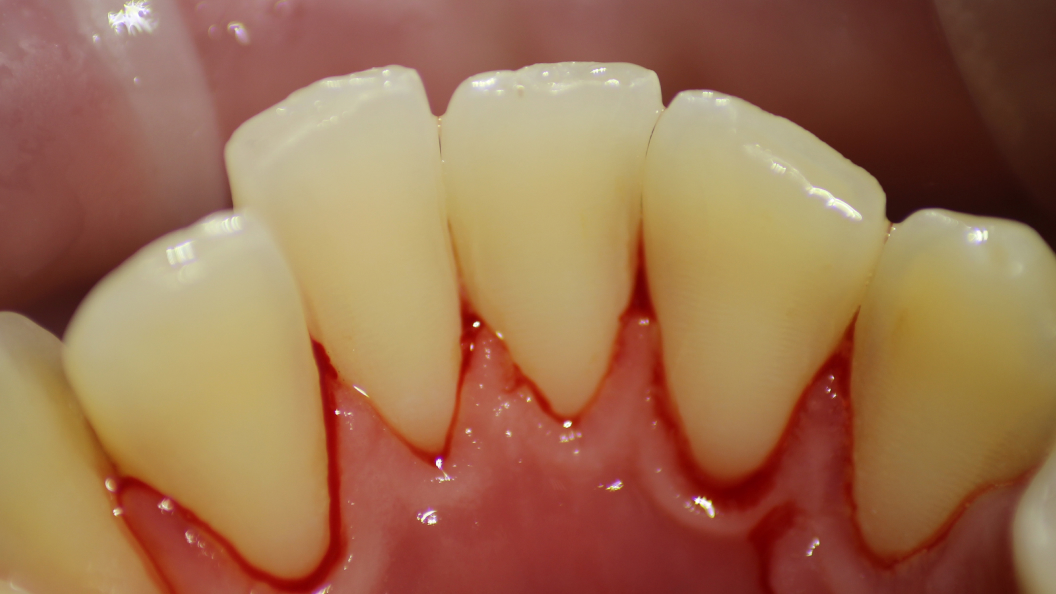

До и после лечения

В клинику обратился пациент с жалобами на кровоточивость дёсен, неприятный запах изо рта. Врач Галухина Карина Николаевна осмотрела пациента и выявила простой маргинальный гингивит. Было решено провести процедуру профессиональной гигиены полости рта. В заключение пациенту было рекомендовано использование зубной нити и ирригатора.